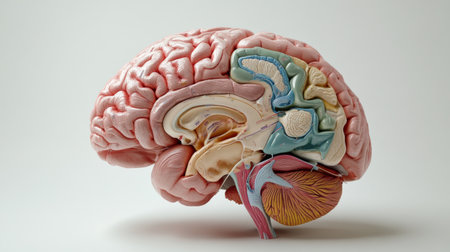

This detailed cross-section of the human brain illustrates its anatomical features, making it ideal for educational purposes in neuroscience and medicine.

An educational scene featuring a human brain cross-section with labeled parts, alongside medical charts and anatomical references for a classroom setting.

This close-up photo captures the intricate details and structures of a human brain, Cross-sectional image of a human brain, AI Generated

An educational scene featuring a human brain cross-section with labeled parts, alongside medical charts and anatomical references for a classroom setting.

An educational scene featuring a human brain cross-section with labeled parts, alongside medical charts and anatomical references for a classroom setting.